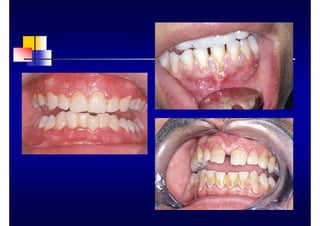

CLINICA

„ Bolsa ósea

„ Reabsorción ósea

„ Furcaciones: grados I, II, III

„ Movilidad y migración: grados I, II, III

„ Bolsa gingival

(relativa o falsa)

„ Bolsa periodontal

(absoluta o verdadera)

„ Supraósea

„ Infraósea

„ Simple

„ Compuesta

„ compleja